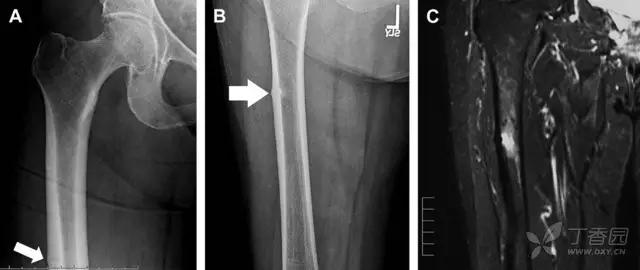

非典型股骨骨折

另一种易漏诊的骨折是非典型股骨骨折,这种骨折与长期服用双膦酸盐相关,常发生在使用双膦酸盐 3 年以上的患者。前驱症状表现为腹股沟痛或大腿痛的患者中,60%~70% 被错误地认为由腰背痛或髋关节炎引起。

这种骨折的一个典型表现为火山口状骨膜隆起及一横行透亮带。值得注意的是,超过 50% 的患者表现为股骨干完全骨折。由于 50%~60% 的患者会累及双侧,所以一旦一侧下肢确诊,需行对侧下肢检查。

图 10 老年患者长期服用双磷酸盐引起的骨折。A 髋部正位片,箭头所示,股骨外侧皮质存在横行透亮带。B 后续的股骨 X 线片示局灶性骨膜反应,以及此类骨折的特征性表现-火山口状骨膜隆起(箭头)。C MRI 冠状位 STIR 序列扫描示相应骨折平面的骨髓水肿表现